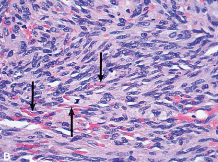

A 45-year-old man presents with painful, purple nodules on the dorsal surface of his left hand. A biopsy displays atypical spindle-shaped neoplastic cells and extravasated red cells. Similar lesions are found in the lymph nodes and liver.

Disease and etiology?

(note extravasated red cells in image)

Kaposi Sarcoma

HHV-8

(note extravasated red cells, cytologic atypia of spindle cells, and formation of slit-like spaces)